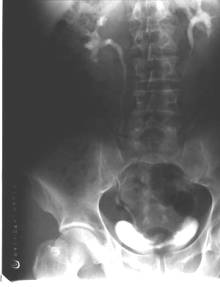

病历摘要:男,54岁病史:间歇性肉眼血尿伴下腹部隐痛7月余。为全程血尿,浓茶色,并有尿频尿急尿痛。当地医院曾造影检查示“膀胱结石”,入院前3天当地医院检查示“膀胱肿瘤”体查:心肺腹无明显阳性体征,双肾区无叩痛,双输尿管行程无压痛点,膀胱区未见肿胀、隆起实验室检查:尿常规:淡黄色,混浊,潜血大量,镜检白细胞370/μl(↑)